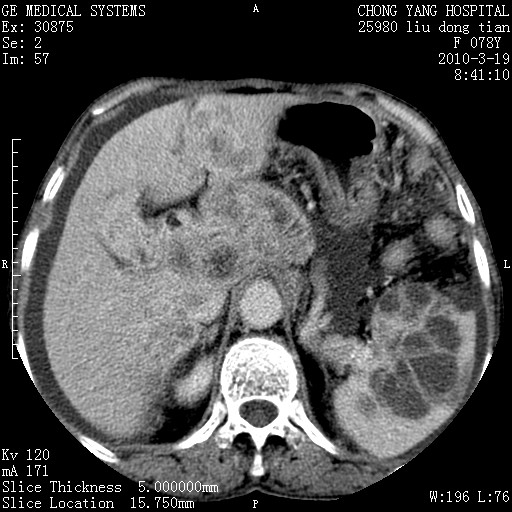

标题: CT25199:F 78Y 腹胀半年 消瘦乏力 [打印本页]

胆囊壁增厚并明显强化,胆囊癌伴多发转移瘤可能性大,淋巴瘤不除外,右肾囊肿,胸腹水.

考虑nhl,肝、脾、腹膜腔及腹膜后多发淋巴结受侵,腹水,右肾囊肿,慢性胆囊炎,右侧少量胸腔积液。

胆囊有软组织影有强化,支持胆囊癌,肝脾、腹膜后淋巴结转移。

nhl的淋巴结多围绕主动脉,而且主动脉会移位,所以不考虑nhl。

分开来讲:肝左叶、尾叶病灶有不均强化像肝癌;

脾脏病灶无强化,像多发囊肿或淋巴管瘤,不除外淋巴瘤(低强化);

胆囊增生性病变:胆囊癌,腺肌增生症,慢性胆囊炎;

肝门、胰腺头、腹膜后多个团块: 淋巴瘤,转移;

腔静脉肝内段细小有无布加可能?

一元论最好了 淋巴瘤所致改变; 胆囊癌转移不像,胆囊周围肝组织清晰,肝癌淋巴结转移?三元论都不止。

最后报的胰头癌多发转移,脾脏单独考虑囊肿或淋巴管瘤。